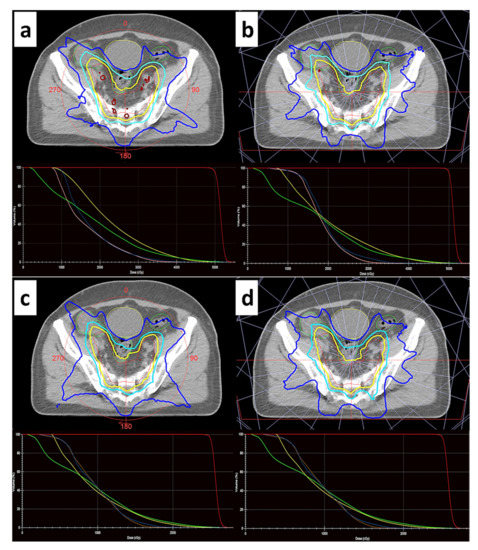

2.2. Treatment Protocols, Techniques and Plan Optimization

3.1. Dosimetric Analysis and Comparison